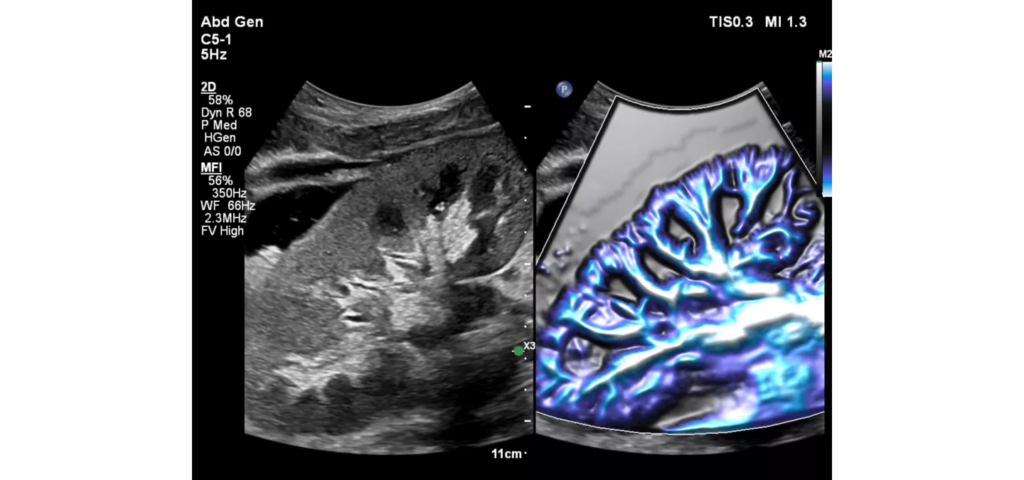

Philips EPIQ Elite ultrasound features an exceptional level of clinical performance, workflow, and advanced intelligence to meet the challenges of today’s most demanding practices. The EPIQ Elite platform brings ultimate solutions to ultrasound, with clinically tailored tools designed to elevate diagnostic confidence to new levels.